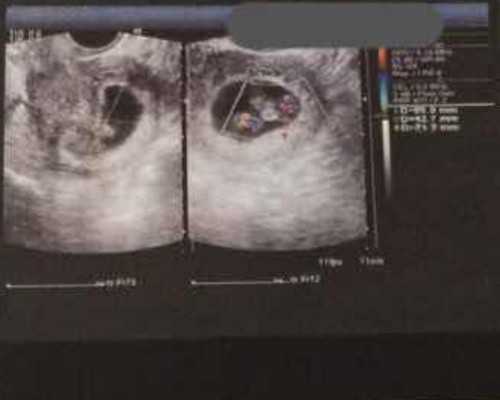

这个问题,首先要明确的是,每一对夫妻的试管婴儿成功几率会因为各种因素的不同而不同,无法作出统一的回答。然而,一般来说,在四川广安的试管婴儿中,根据多年经验有统计,以35岁以下夫妻组合为主,试管婴儿成功几率可以达到65-70%左右。同时,36~40岁的年龄组合,试管婴儿成功率也可以达到50-60%。值得注意的是,当夫妻组合中有一方超过40岁,即使是四川广安高科技试管婴儿,成功率也会因为好子细胞减少等因素出现下降。此外,试管婴儿手术的前期准备,如医院水准、技术水准、操作水准等等,都会影响最终结果,也会直接影响试管婴儿成功率。因此,通常来说,在进行试管婴儿之前,一定要询问专业的医生,夫妻双方的身体情况、试管婴儿医院的水准等等,做好全方位的准备,才能最大程度提高试管婴儿成功几率。